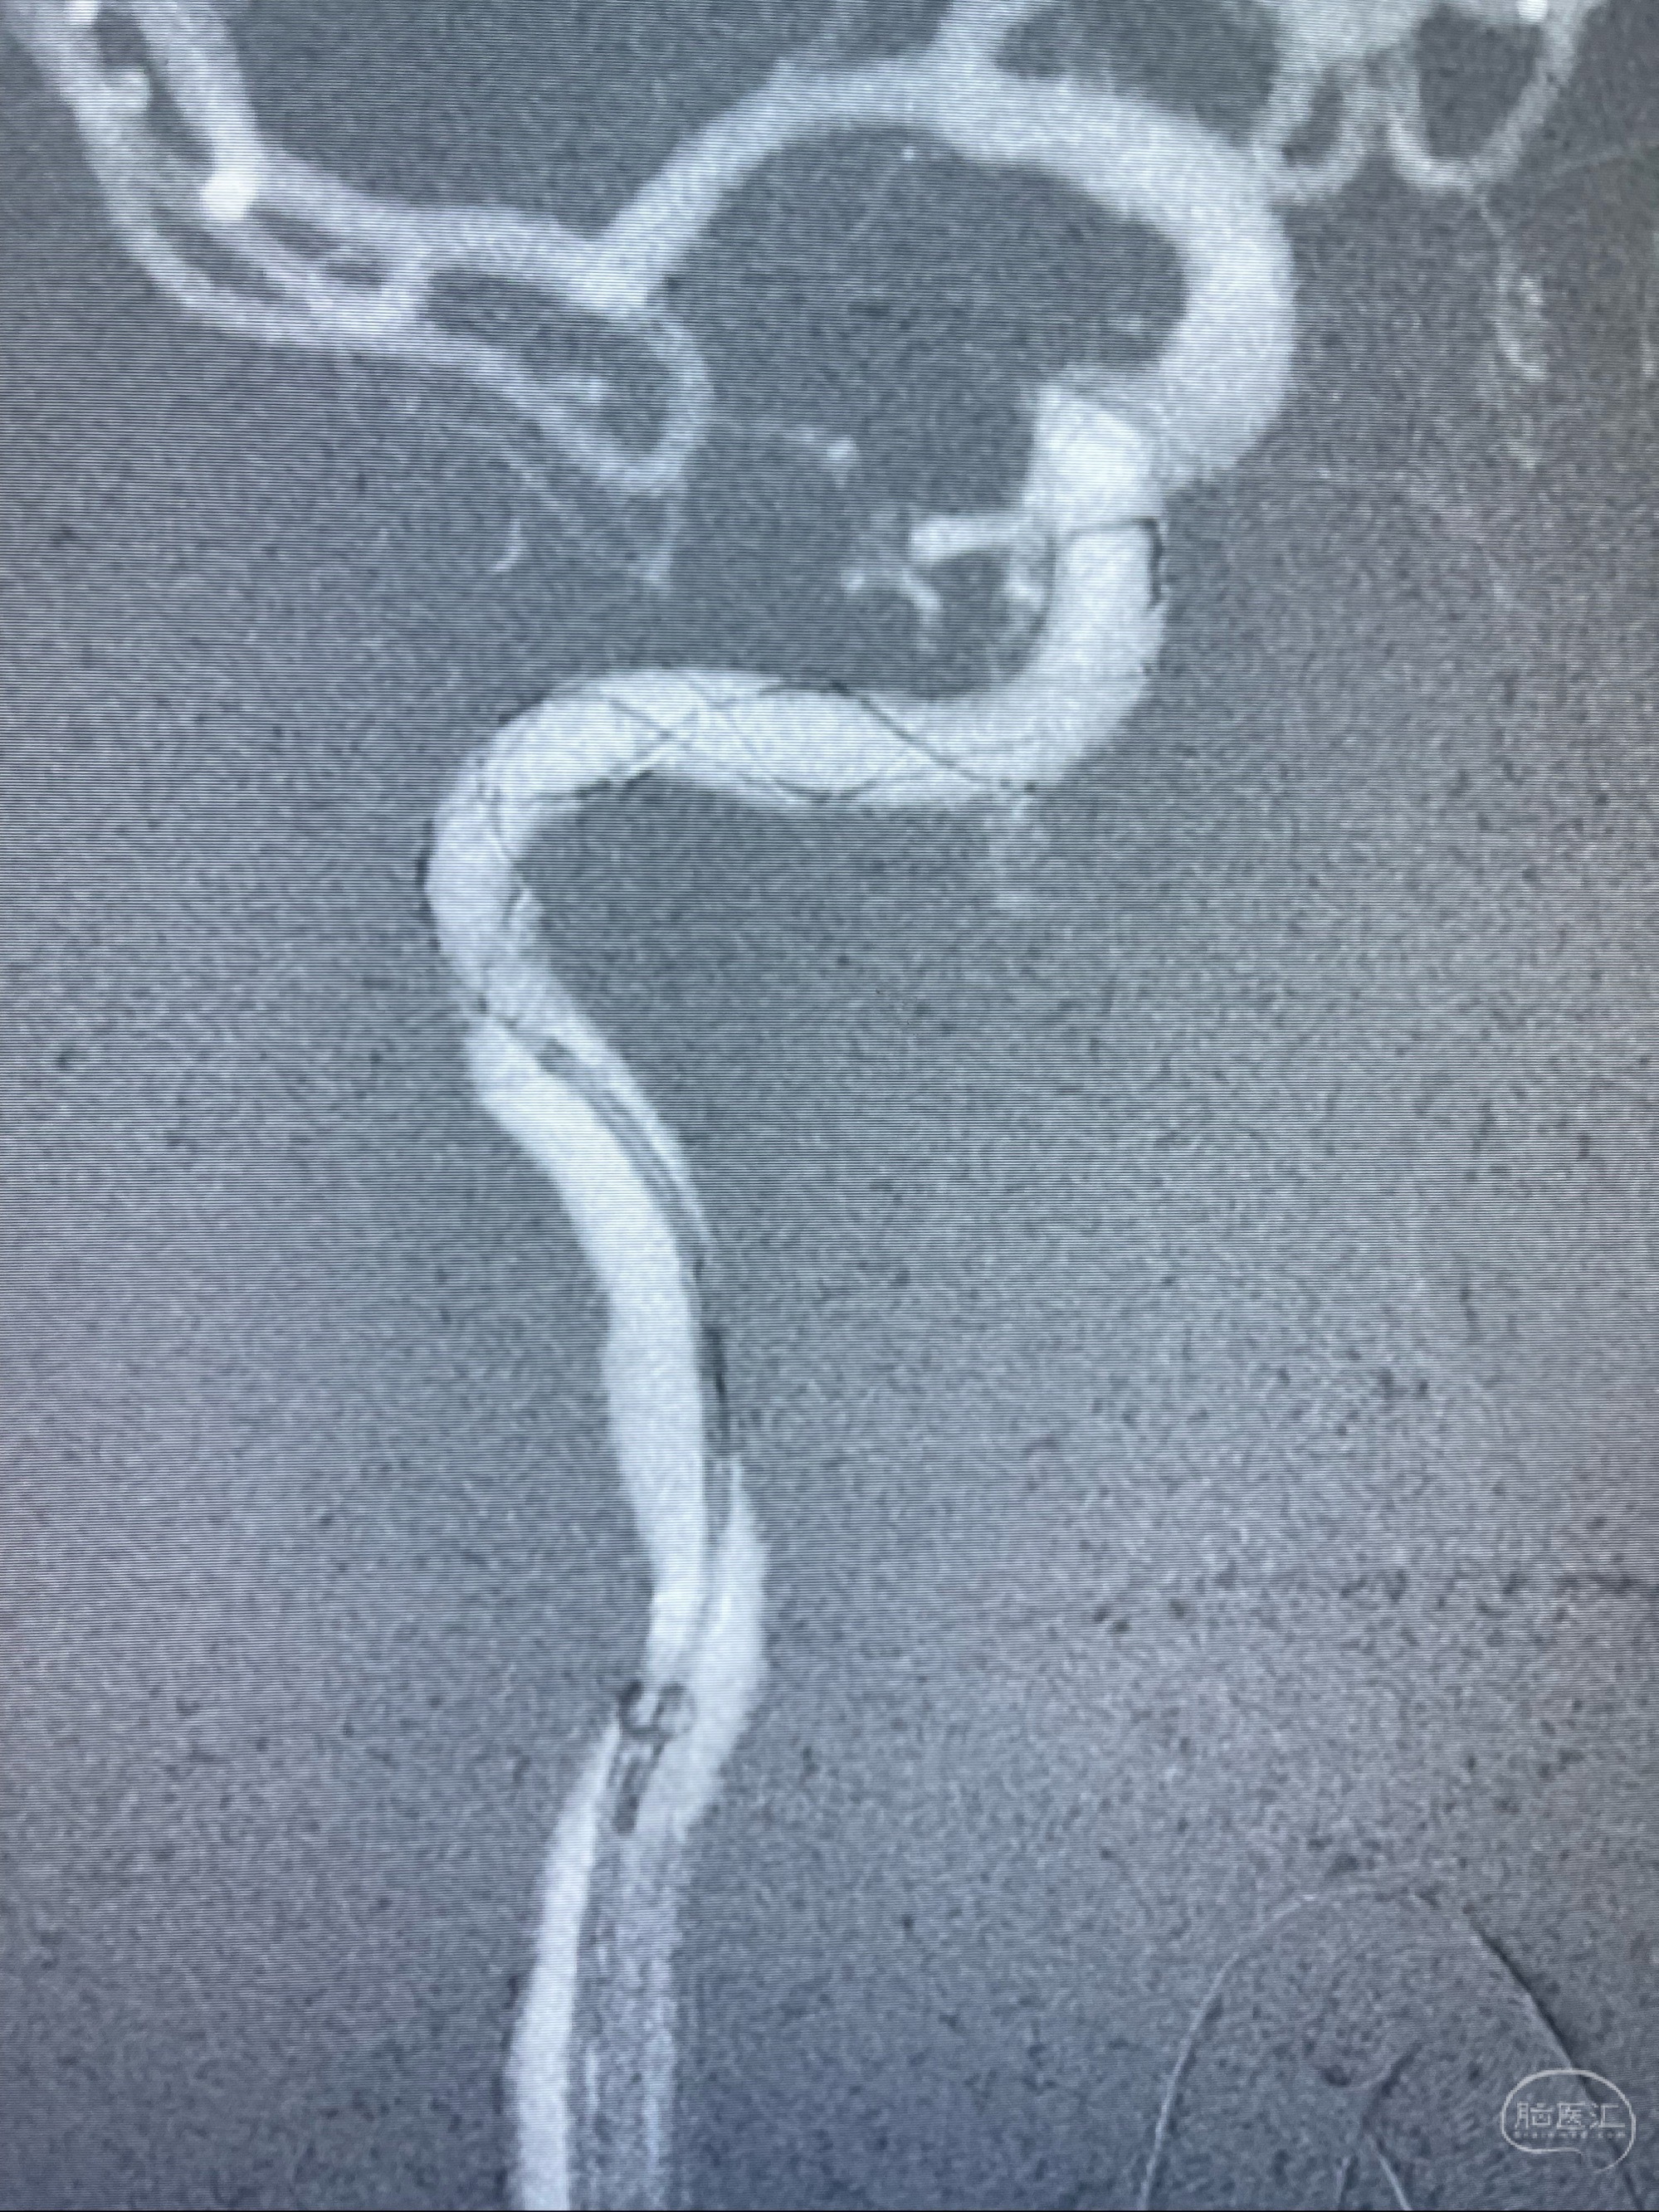

2023-07-10DSA:右侧颈内动脉岩骨段夹层伴中偏重度狭窄改变,左侧颈总动脉闭塞、右侧颈外动脉由右侧肋颈干甲颈干吻合代偿

箭头所示为颈内动脉岩骨段重度狭窄,结合MRI,考虑为肿瘤侵犯右侧颈内动脉

箭头以近至支架段管腔不规则狭窄

MRI:显示肿瘤侵犯右侧颈内动脉岩骨段上下,向下至原颈内动脉支架远心段,向上至颅底